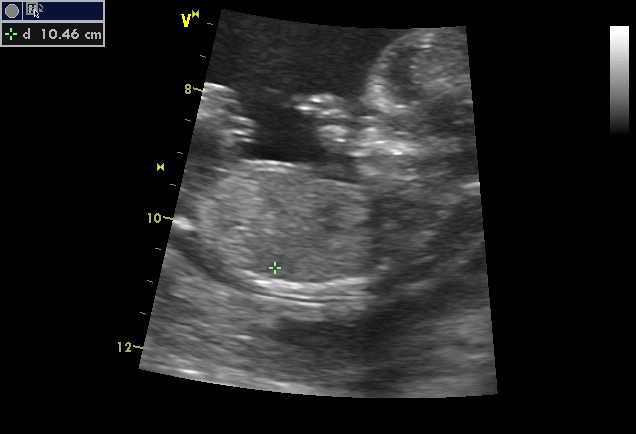

Ahojky maminy, omlouvám se, že jsem nedala vědět už včera jak jsme dopadli na tom screeningu. Pak doktor byl velice příjemný. Vše nám na ultrazvuku ukázal a vysvětlil. Koukal na obě hemisféry v hlavičce, na průtok krve velkými tepnami a dokonce i chlopněmi v srdíčku. Bylo to nepopsatelné. Nakonec jsme se dozvěděli, že máme riziko vrozené vývojové vady z krve a dle mého věku v době porodu (31) 1/840, ale tím ultrazvukem, že se to riziko výrazně snížilo. Tak máme ohromnou radost. Jinak pohlaví miminka nám prý sdělí až za měsíc, že je ještě brzy. Hlavně je to neposeda, Měl problémy miminko vůbec zkontrolovat. Nakonec nám miminko i zamávalo. A hlavně se mi líbilo, že doktor od začátku mluvil o miminku a ne jakoby o nějaké věci. Takže za mě screening jedině doporučuji.